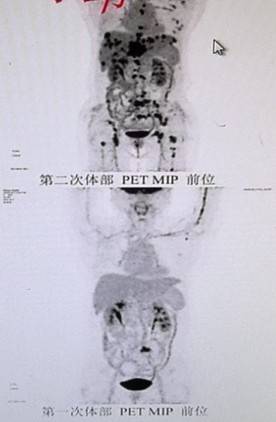

2025年1月复查发现肝脏多发转移及多发骨转移,累及枕骨、肱骨、股骨、肩胛骨及多个椎体。团队第一时间对肝转移灶行穿刺活检及二代测序。检测显示,患者携带PIK3CA的G118D(78.3%)及Y1021C(61.4%)双突变,并伴FGFR1、JAK2、CCND1、PIK3CA扩增,以及RAD51D、BRCA1、CDK12、NF1等基因缺失。肝转移灶免疫组化出现雌激素受体阴性、孕激素受体弱阳性、HER2低表达(免疫组化2+,荧光原位杂交阴性),提示转移灶受体表型发生改变(异质、演变)。

2025年8月,患者出现脑部多发转移(额叶、小脑及颅骨)。在完成颅内放疗后,基于其PIK3CA突变及扩增背景,考虑到患者基础情况较差,无法耐受化疗,且既往激素受体存在表达,参考INAVO120研究治疗模式,医疗团队果断采取联合靶向策略。